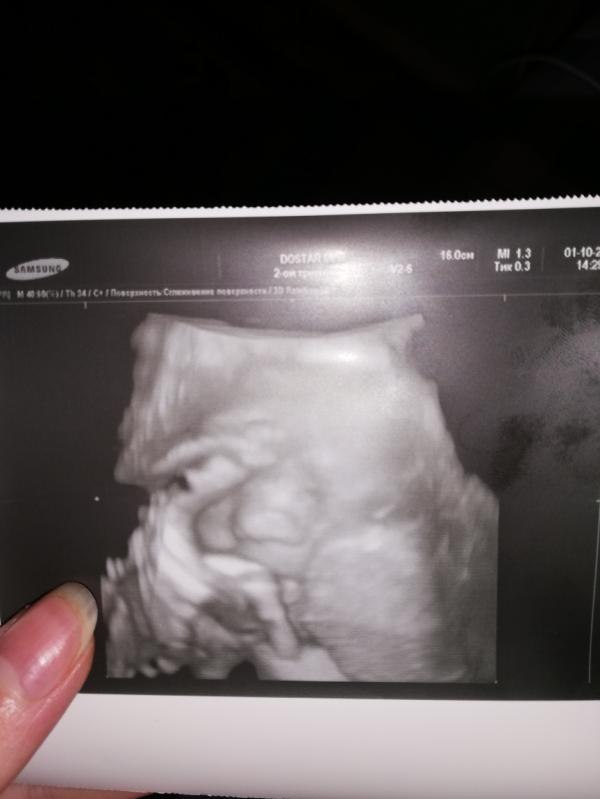

post image 2

Сходила сегодня к Раченковой, она такая классная, спасибо что посоветовали) наша девочка с длинными ногами😃 закрывает ножкой лицо, вся в меня) я тоже родилась с длинными ногами) вообщем советую её теперь всем) не дорого и все внимательно ❤️❤️❤️❤️

Это допплер, по поводу 4 D лучше позвоните, узнайте

Да заранее лучше записаться, 4 тыс стоит допплер, и фото она сделала за 500 тн